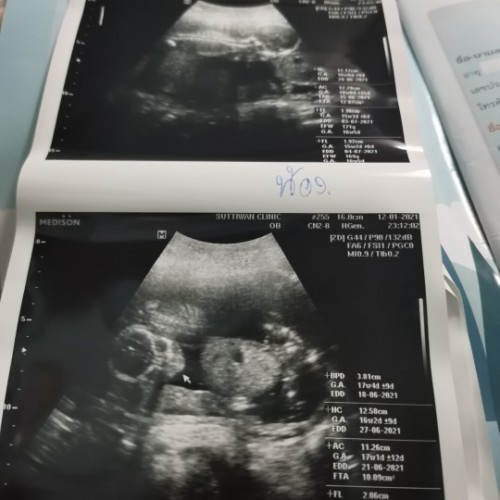

กำหนดคลอด 27 มิย ได้ลูกชายค่ะ😊😊

หมอบอกกำหนดคลอดวันที่ 25มิ.ย คะ ตอนนี้26 สัปดาห์ 4วันแล้วคะ